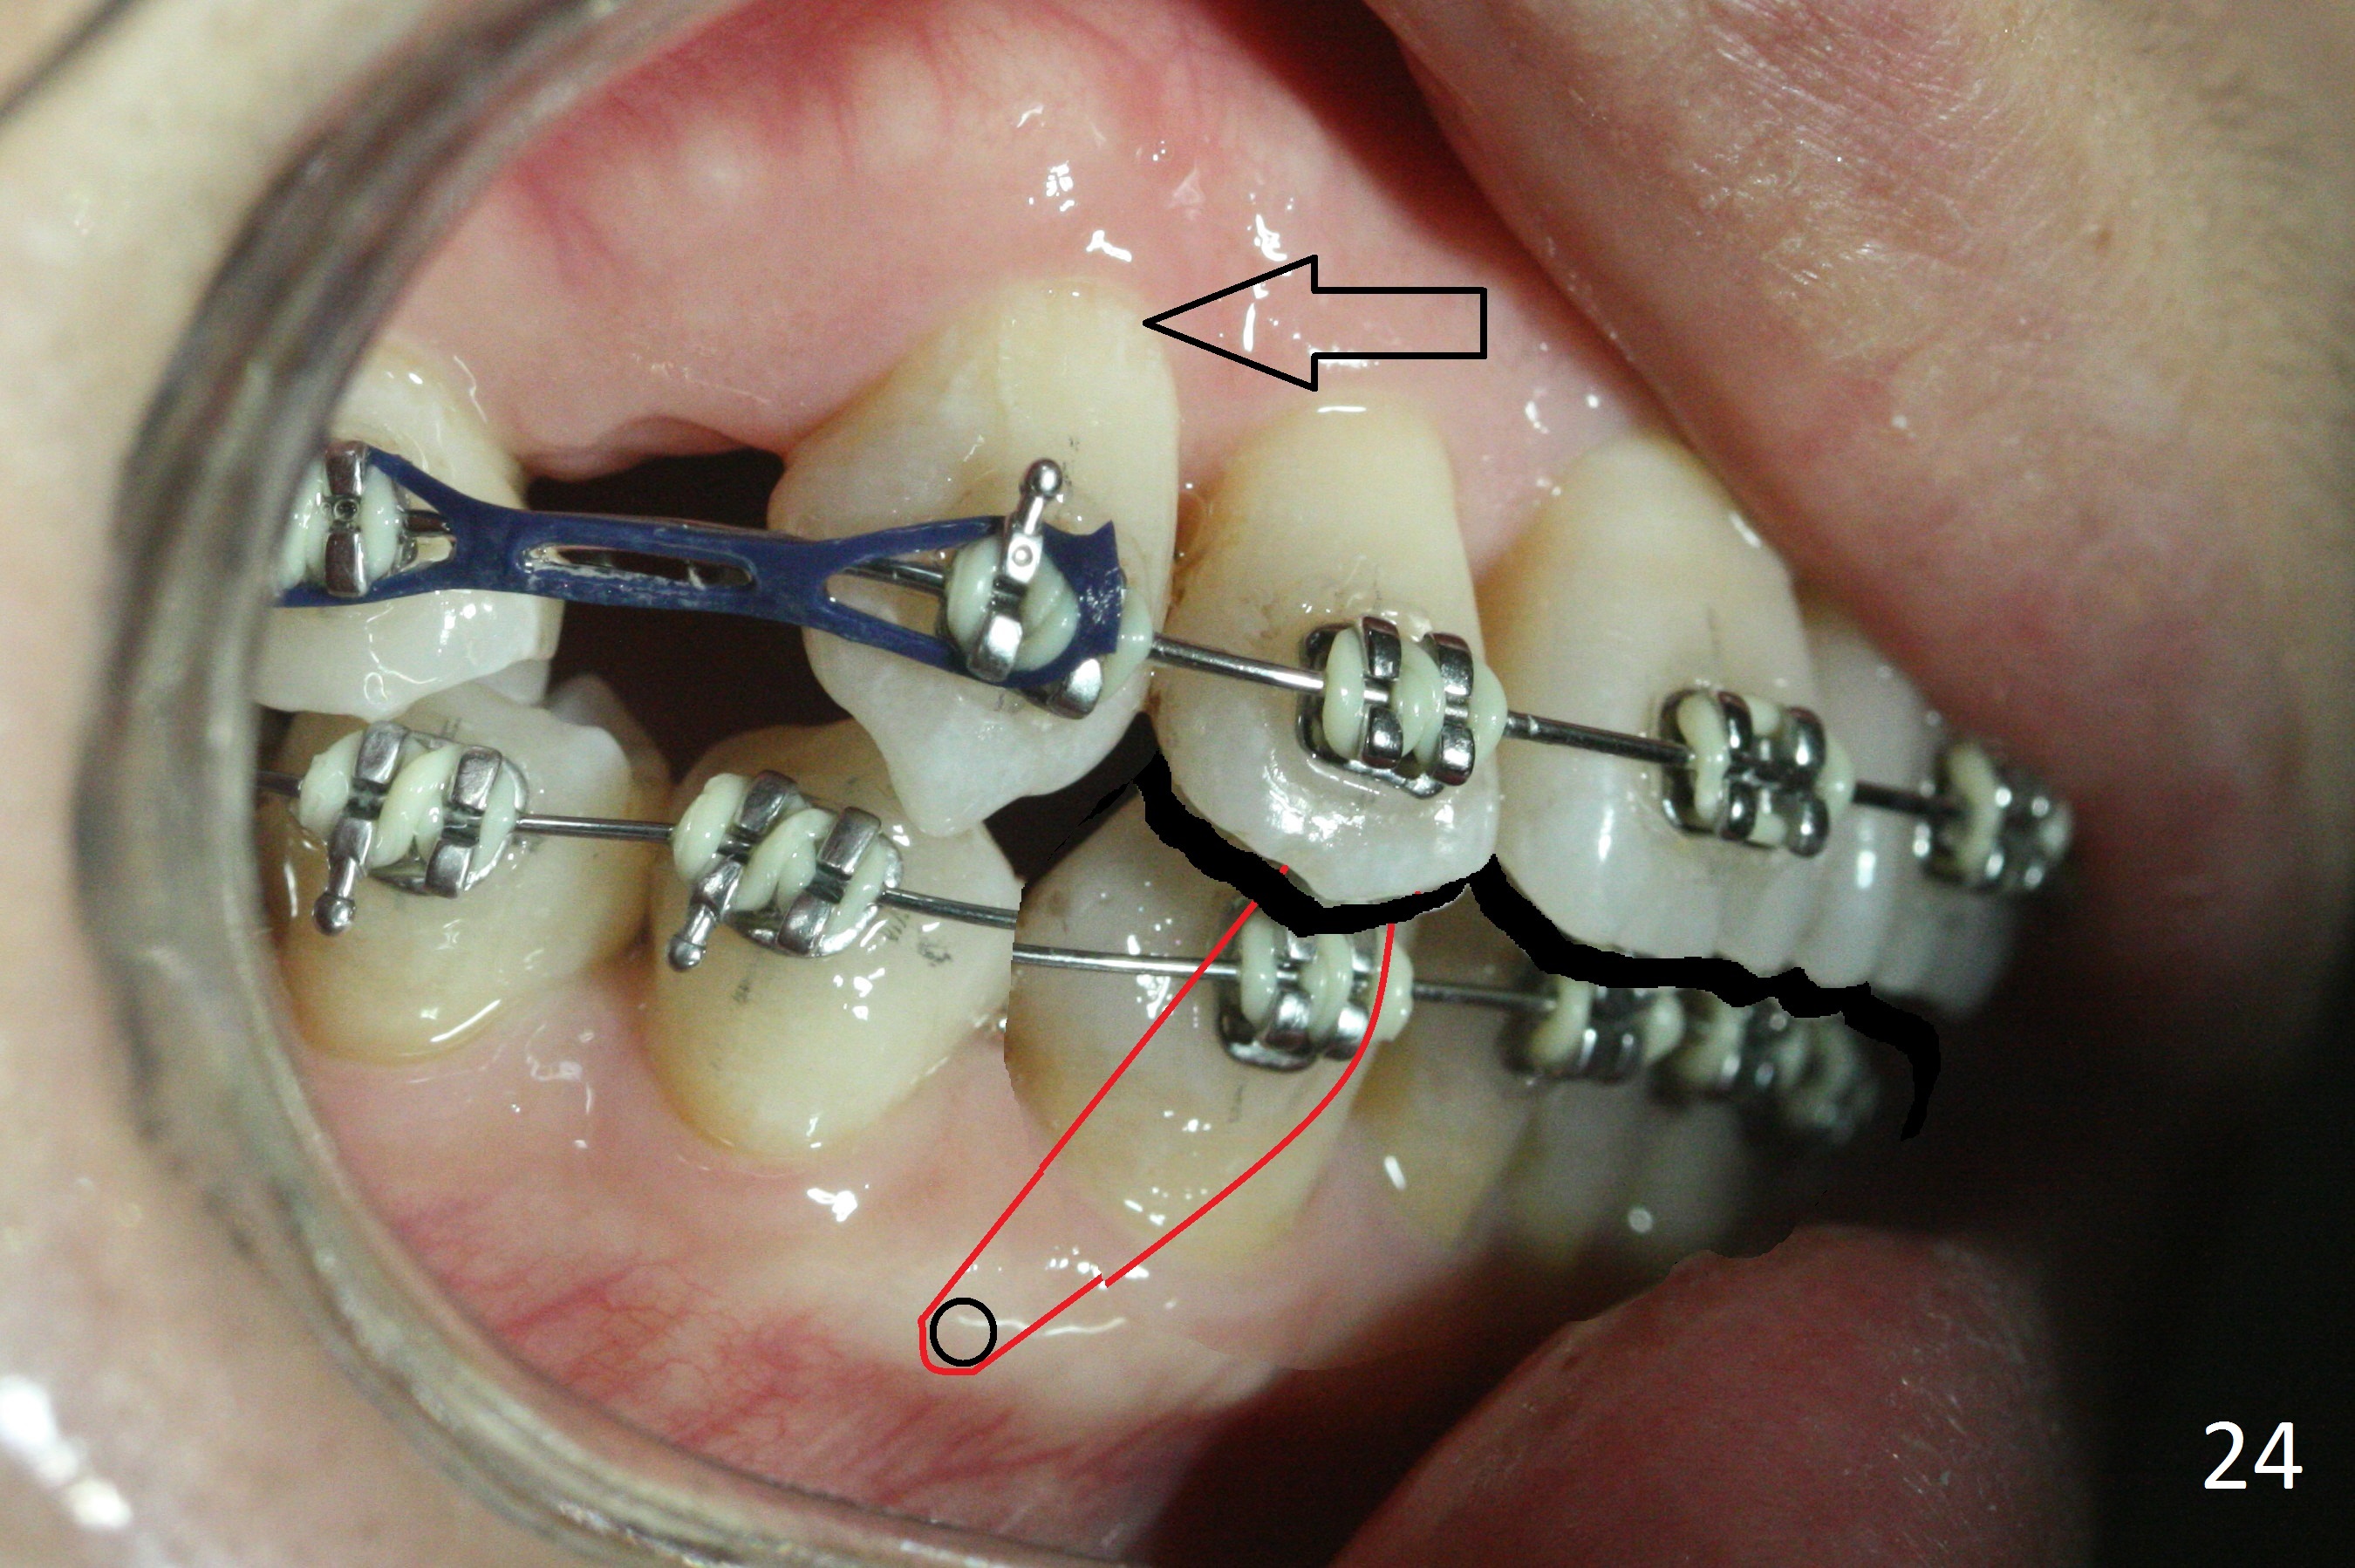

The rotation of the upper canines is not corrected much in the next 3.5 months (Fig.21, as compared to Fig.18). Distalization of the upper right canine is implemented by power chain, but this is not sufficient because of the anterior deep bite. Note the tension of 18 niti wire between LR 3 and 4 (^). Mini implants are going to be placed mesial or distal to L3s (Fig.22,23 circles) to intrude the lower anterior teeth with elastic or power chain (Fig.23 red line, 24 black area). The upper anteriors will have space to be distalized (Fig.24 arrow). If necessary, proximal reduction will be accomplished at LR3 (extra wide, Fig.25 black outline) for further overjet correction (arrows).